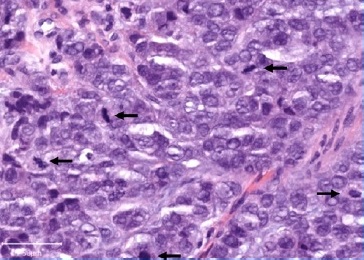

On physical evaluation, a painless 1.2-cm firm nodule was palpable sublingually, leading to the presumptive diagnosis of sialolithiasis. The mass was removed and submitted to pathological examination. Grossly, the lesion was firm and grayish with irregular borders (Figure 2). Histopathology showed a malignant lesion comprising neoplastic epithelial cells arranged in small nests with a large central area of chondroid matrix (Figure 3). The epithelial cells were large, with hyperchromatic and pleomorphic nuclei presenting a high mitotic rate (Figure 4). At the edge of the fragment, salivary parenchyma exhibiting ductal ectasia with scant inflammatory cells was identified.

Figure 4 High magnification of the tumoral cells showing high-grade cytological features and several mitoses (arrows), HE